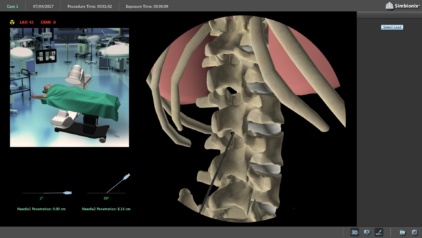

The Spinal Cord Stimulation (SCS) module was developed to help train surgeons on the procedural steps and pathologies relevant to SCS procedures.

- A 3D anatomical map assists in learning the anatomy to position the needle accurately

- Radiographic imaging and C-arm control helps to confirm the needle position